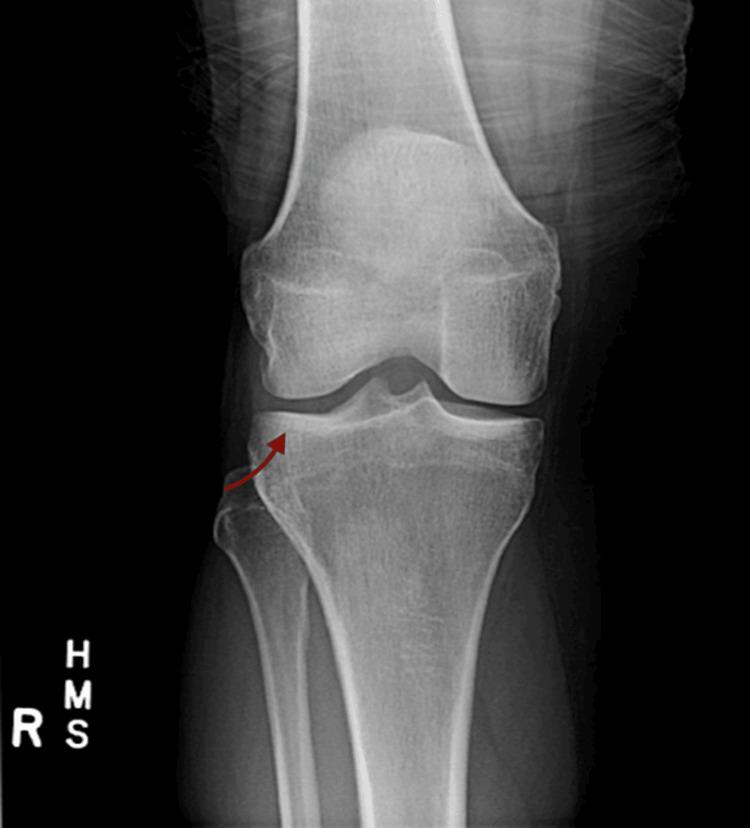

In this case report, we highlight a rare case of palindromic rheumatism (PR) presenting as polymyalgia rheumatica (PMR). Many challenges and complexities are associated with diagnosing and treating PR. Literature reviews showed only a few case reports of this unique presentation. PR has a distinct presentation that often goes unnoticed and is misinterpreted by medical professionals. A more thorough clinical approach is required to identify and treat this condition. We hope sharing such uncommon cases will help the medical community better understand PR and develop improved diagnostic and therapeutic options. This case also demonstrates the need for further research to better understand the pathogenesis of this uncommon condition.

在本病例报告中,我们着重介绍了一例表现为风湿性多肌痛(PMR)的罕见回纹型风湿症(PR)病例。PR的诊断和治疗存在诸多挑战与复杂性。文献综述显示,关于这种独特表现的病例报告仅有少数几例。PR具有独特的临床表现,常常未被注意到,且被医学专业人员误解。需要更全面的临床方法来识别和治疗这种疾病。我们希望分享此类罕见病例将有助于医学界更好地了解PR,并开发出改进的诊断和治疗方案。该病例还表明需要进一步研究,以更好地理解这种罕见疾病的发病机制。